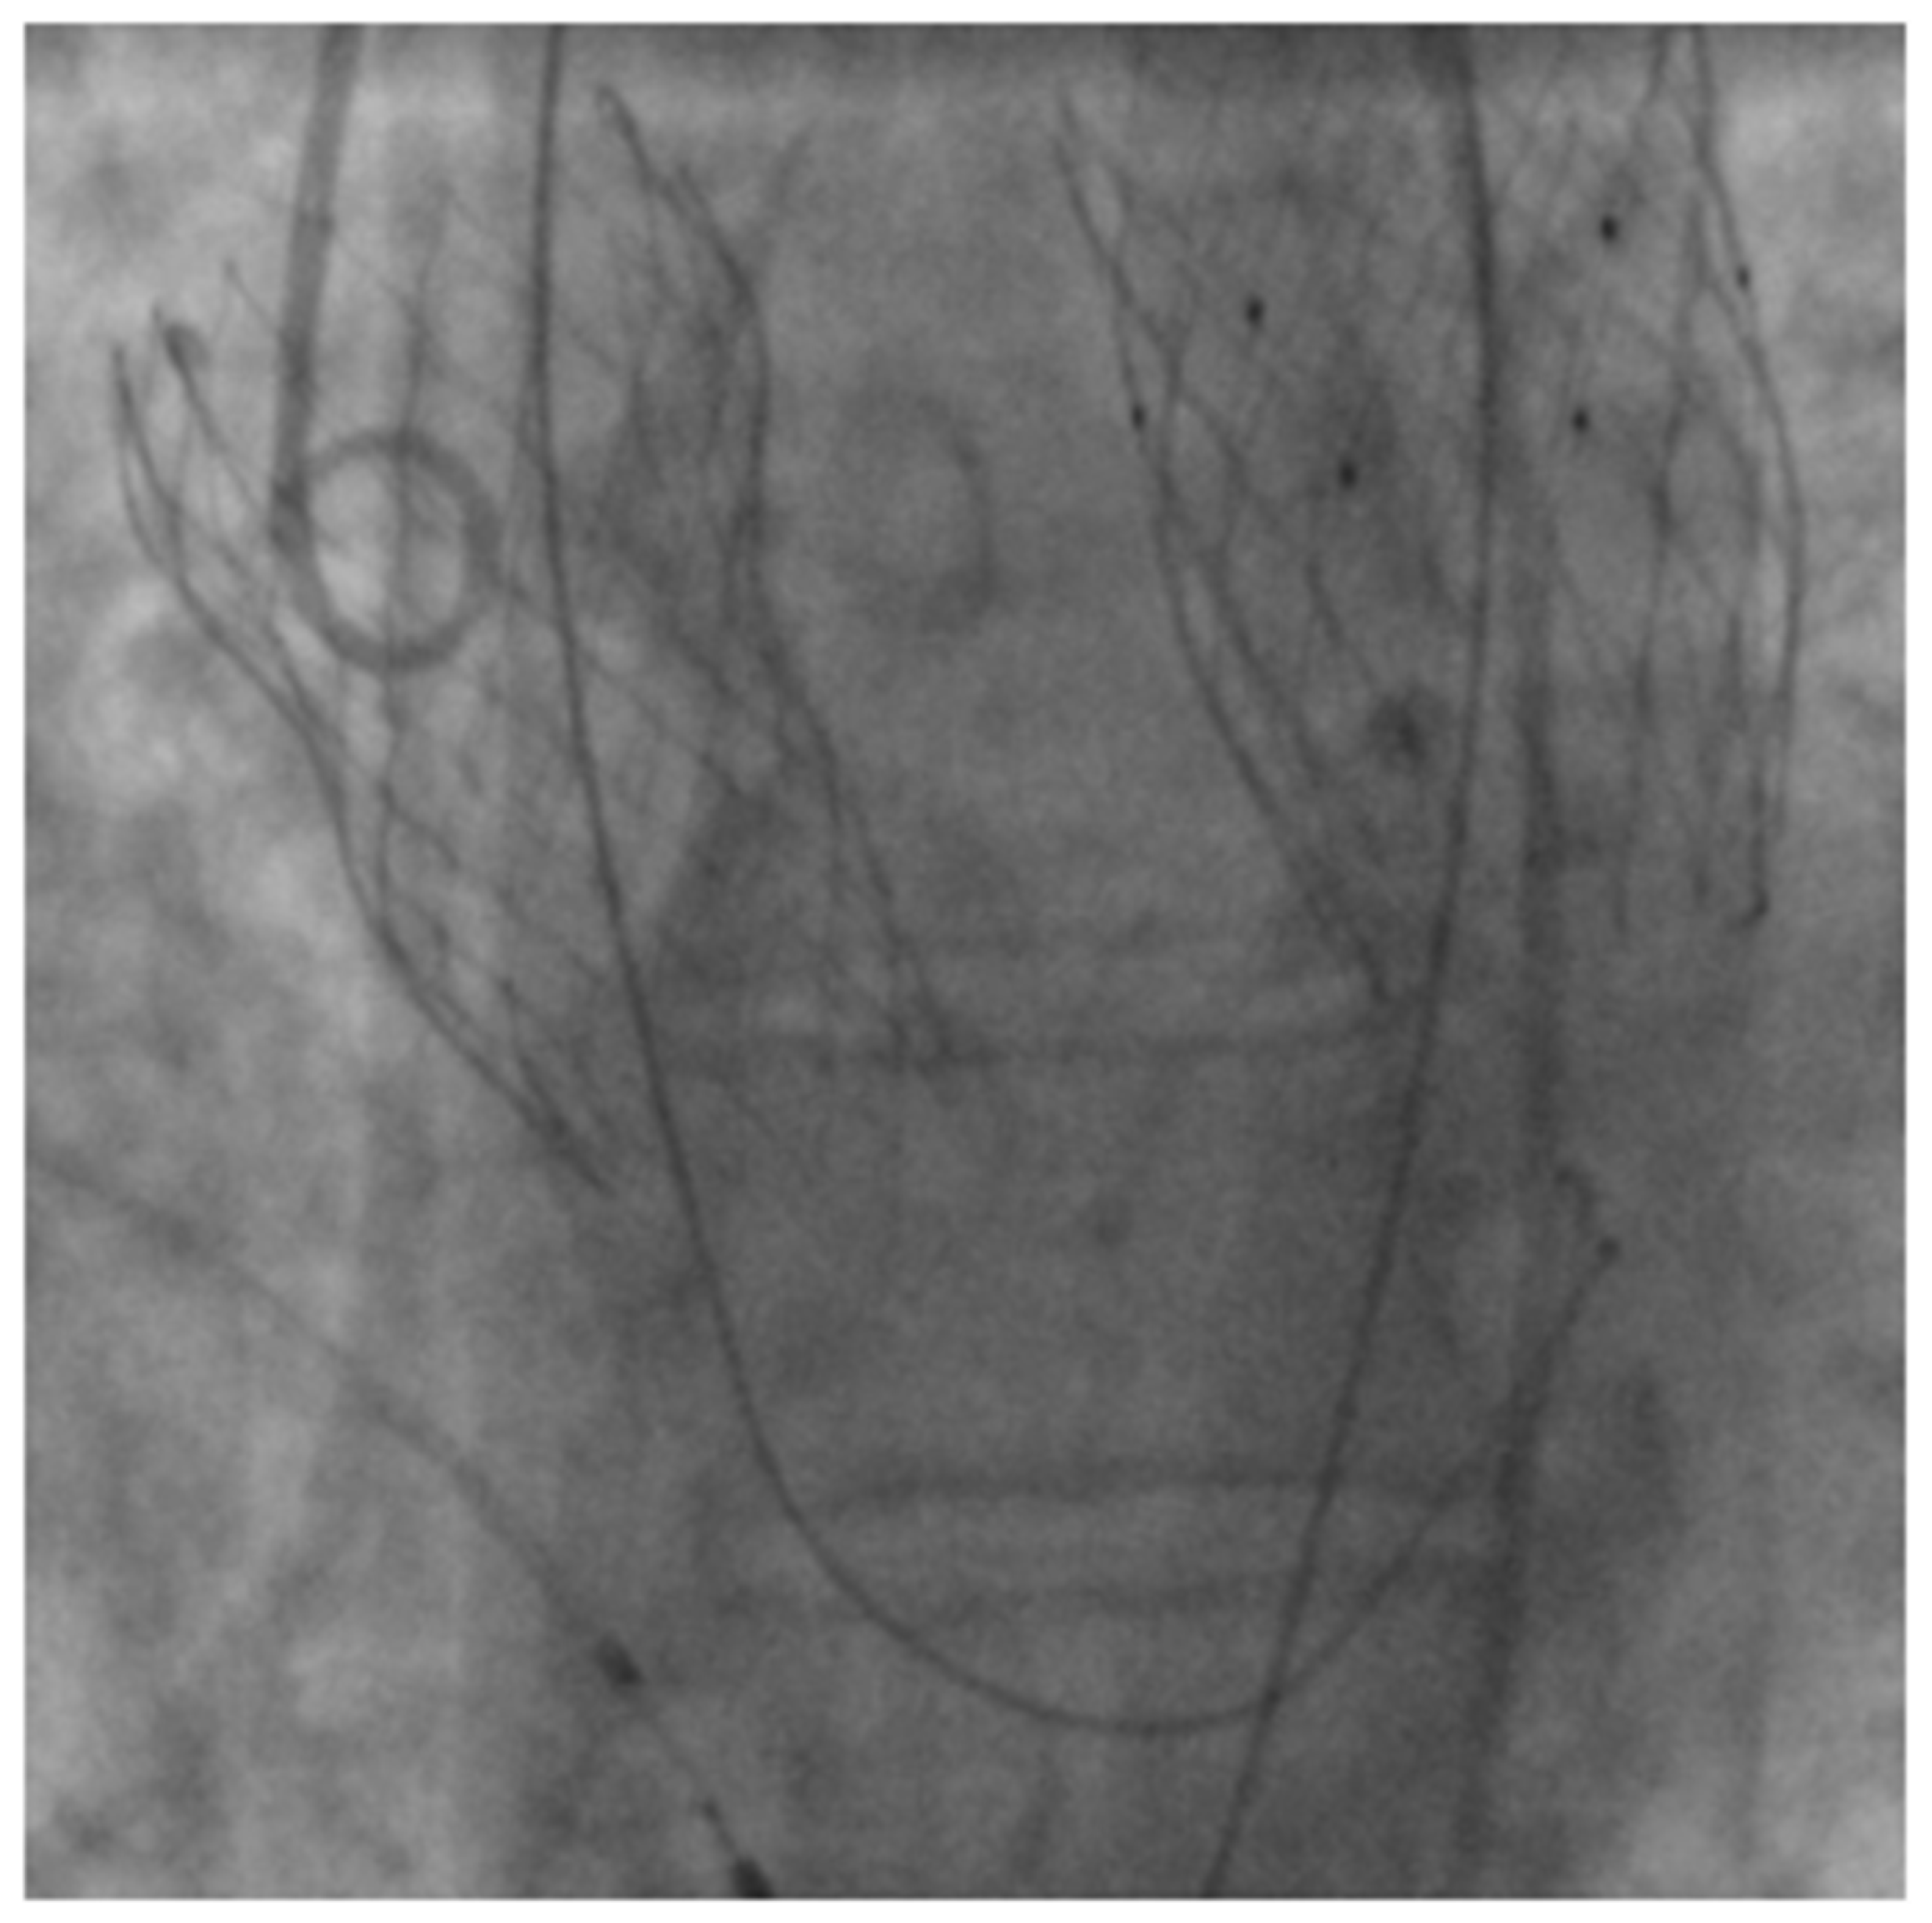

Spectral CT Imaging of Prosthetic Valve Embolization after Transcatheter Aortic Valve Implantation

D’Angelo, T.; Vizzari, G.; Lanzafame, L.R.M.; Pergolizzi, F.; Mazziotti, S.; Gaeta, M.; Costa, F.; Di Bella, G.; Vogl, T.J.; Booz, C.; et al. Spectral CT Imaging of Prosthetic Valve Embolization after Transcatheter Aortic Valve Implantation. Diagnostics 2023, 13, 678. https://doi.org/10.3390/diagnostics13040678